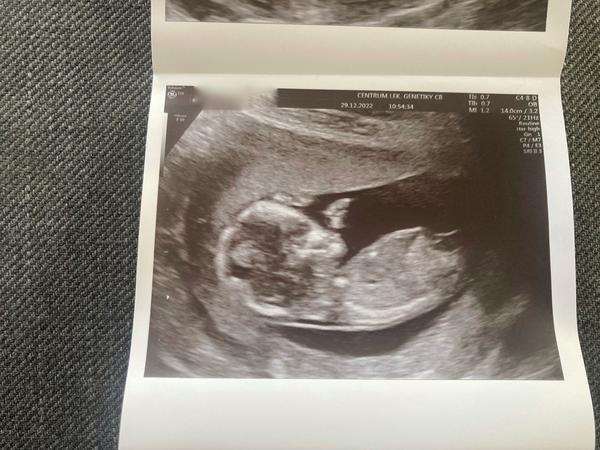

Ahojky holky 🙂 na screeningu nám pan doktor dle první fotky řekl, že to vypadá na chlapečka. Nicméně já si myslim, ze 12tt maji pohlavni hrbolek z tohoto profilu obě pohlaví stejné. Až doma jsme koukali na fotky a z druhé fotky je krásně vidět pohlavní hrbolek. Pan doktor si toho nevšiml, tak jsme se nestihli zeptat jeho😄

Ahoj🙂 13+6 poznal by někdo pohlaví? Dekuju